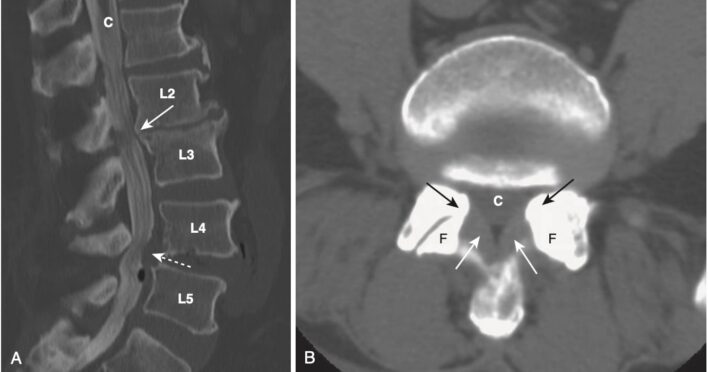

Mỗi đốt sống (hầu hết mọi đốt sống) đều có phần thân bao gồm xương xốp và tủy xương bên trong và phần sau được tạo bởi xương đặc, bao gồm cuống cung, bản cung, các diện khớp nhỏ (facet, mỏm khớp), mỏm ngang và mỏm gai (Hình 1, A).

- Trong hình chiếu thẳng, mỗi thân đốt sống hiển thị hai cuống cung hình oval có thể nhìn thấy được ở hai bên của thân đốt sống. Các cuống cung của L5 thường rất khó nhìn thấy ngay cả ở những người bình thường, bởi vì độ ưỡn của cột sống thắt lưng (xem Hình 1, B).